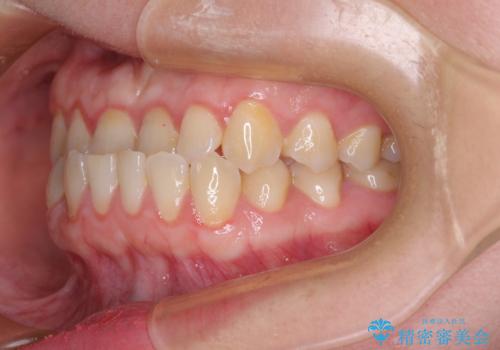

このような咬み合わせの方の多くは、舌の突出癖が強い傾向にあり、反対咬合改善後に開咬となってしまい、なかなか治療が終わらないことがあります。

こちらの患者様は、舌のトレーニングを治療開始前から徹底的に実践していただき、僅か8ヶ月という短期間で治療を終えることができました。